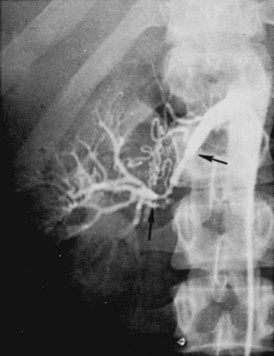

Angiographically, medial fibroplasia demonstrates a typical “string of beads” appearance involving the distal two thirds of the main renal artery and branches (Fig. 39–4). The areas of stenosis are often overshadowed by contrast medium in the microaneurysms, making the degree of actual stenosis difficult to assess. The aneurysms themselves are greater in diameter than the normal renal artery proximal to the disease, and extreme collateral circulation is absent. These are important features in differentiating the lesion from perimedial fibroplasia. Schreiber and colleagues (1984) studied the natural history of renal artery disease due to medial fibroplasia in 66 patients who were followed with serial angiography. Progressive renal artery stenosis (RAS) occurred in 22 patients (33%), and, contrary to an earlier report, this occurrence was no different whether patients were older or younger than 40 years. Significantly, there were no cases of progression to total arterial occlusion in this group. Also, clinical follow-up revealed that serial decreases in either overall renal function or the size of the involved kidney seldom occurred in patients with progressive medial fibroplasia, suggesting that the risk of losing renal function is relatively small in patients with this disease who are managed medically.

The arteriogram in perimedial fibroplasia may give the appearance of arterial beading, but careful observation shows that the caliber of the normal segment of the vessel is not exceeded by the “bead” (Fig. 39–6). This fact, along with the frequent occurrence of extensive collateral circulation, differentiates this lesion angiographically from that of medial fibroplasia. Perimedial fibroplasia produces severe stenosis, and, although complicating thrombosis or dissection is relatively uncommon, progressive obstruction with ischemic renal atrophy occurs in almost all patients managed nonoperatively.

Figure 39–6 Renal arteriogram in a patient with perimedial fibroplasia shows slightly irregular, yet severe, stenosis of the midrenal artery (arrows) associated with extensive collateral circulation to the kidney. The small size of the arterial irregularities and the presence of collateral circulation distinguishes this lesion radiographically from medial fibroplasia.

(From Novick AC. Renal vascular hypertension in children. In: Kelalis PP, King LR, Belman AB, editors. Clinical pediatric urology. Philadelphia: WB Saunders; 1984.)